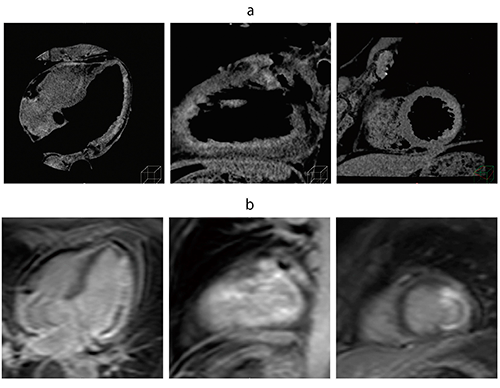

また,Ziostation2の最新バージョンでは,今までのT1マップの問題点となっていた,造影前と造影後の位置ズレを合わせる方法として,非剛体レジストレーションも搭載し,精度の高いECVを算出することが可能となった。さらに,ECVマップやT1マップの画像をDICOM画像として保存(図2)することも新たに可能になった。本誌2015年4月号の当社技術解説から,飛躍的に操作性の向上および機能が追加され,より多くの施設で有効に活用いただくことができる製品として,さらに進化を遂げている。

図2 DICOM保存したT1マップ(a)とECVマップ(b)